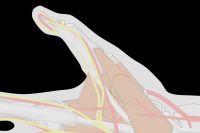

| A key issue is orienting the base of

the flap so that the flap comes to lie perpendicular

to the recipient site. This is best planned

in reverse using a template. This is helpful to also

plan the orientation change resulting from donor site

closure. |

| The goal is to

position the flap against the recipient bed without

tension or torsion. In addition to proper alignment, two key points are: ¤ Adduct the thumb basal joint to bring the flap to the finger to reduce flap tension. ¤ Flex the finger MCP joint to reduce PIP flexion. |